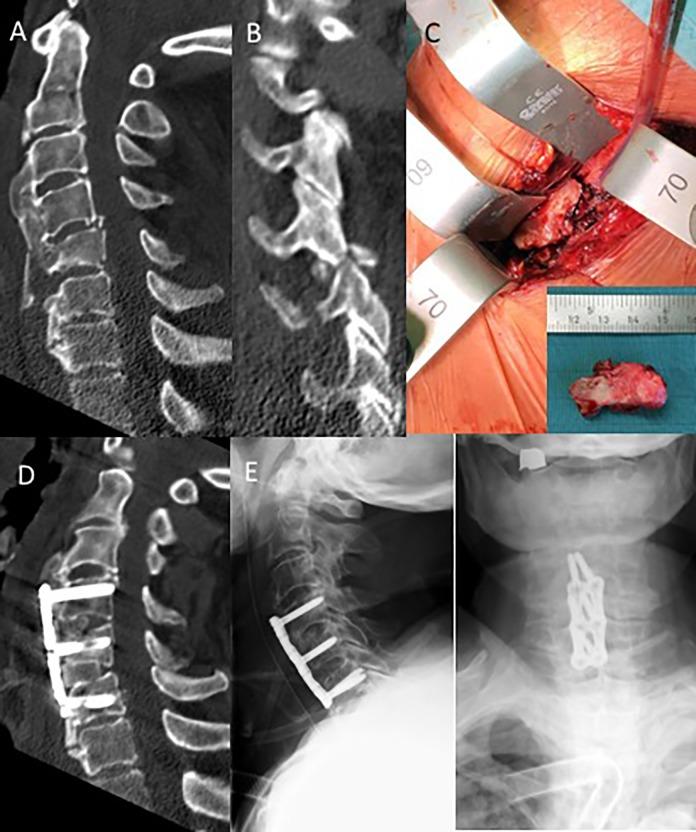

Nondisplaced fractures can be missed easily using conventional X-rays. Thus, computed tomography (CT) scans are recommended for all trauma patients with ASD. In doubt or presence of any neurologic involvement additional magnetic resonance imaging (MRI) scans should be obtained. Spine precautions should be maintained all times and until definitive treatment (<24 h). Nonoperative fracture treatment is not recommended given the mechanical instability of the most commonly seen fracture patterns (AOSpine B- and C-type, M2) in patients with ASD and inherent high risk of secondary neurologic deterioration. For patients with ankylosing spondylitis (AS) or diffuse idiopathic hyperostosis (DISH) sustaining cervical spine fractures, a combined anterior-posterior instrumentation for fracture fixation is recommended. Closed reduction and patient positioning can be challenging in presence of preexisting kyphotic deformities. In the thoracolumbar (TL) spine, a posterior instrumentation extending 2 to 3 levels above and below the fracture level is recommended to maintain adequate reduction and stability until fracture healing. Minimally invasive percutaneous pedicle screws and cement augmentation can help to minimize the surgical trauma and strengthen the construct stability in patients with diminished minor bone quality (osteopenia, osteoporosis).

使用传统X线片容易漏诊无移位骨折。因此,建议对所有患有ASD的创伤患者进行计算机断层扫描(CT)。如有疑问或存在任何神经受累情况,应额外进行磁共振成像(MRI)扫描。应始终采取脊柱防护措施,直至确定治疗(<24小时)。鉴于ASD患者中最常见骨折类型(AOSpine B型和C型,M2)的机械不稳定性以及继发神经功能恶化的固有高风险,不建议采用非手术骨折治疗。对于患有强直性脊柱炎(AS)或弥漫性特发性骨肥厚(DISH)且发生颈椎骨折的患者,建议采用前后联合内固定进行骨折固定。在存在既往驼背畸形的情况下,闭合复位和患者体位摆放可能具有挑战性。在胸腰椎(TL)脊柱,建议在骨折水平上下各延伸2至3个节段进行后路内固定,以维持充分复位和稳定性直至骨折愈合。微创经皮椎弓根螺钉和骨水泥强化有助于将手术创伤降至最低,并增强骨质量较差(骨质减少、骨质疏松)患者的内固定稳定性。